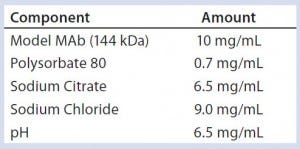

Table 1: Model monoclonal antibody (MAb) formulation

To address those potential compatibility concerns, we conducted a comprehensive study to evaluate the influence of our optimized BFS process and container system on a model monoclonal antibody (MAb) formulation. Table 1 lists the formulation of this model MAb (molecular weight 166 kDa). We used glass vials with uncoated stoppers as controls for this study. Several analytical methods helped us evaluate MAb stability and leachables from the container system (Table 2).